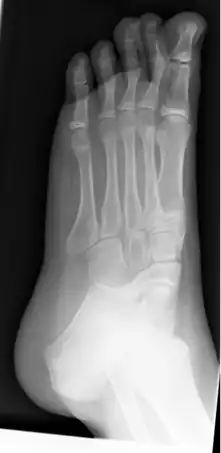

Radiografía de pie izquierdo plano en un niño de 10 años. | ||